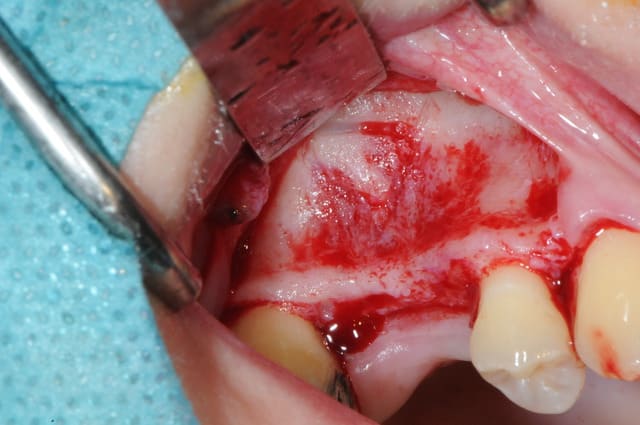

je sais pas si c'est un produit miracle, mais pour les sinus lift, c'est fantastique.

outre le fait de stabiliser un implant dans un sinus type SA4, pas de risque de voir partir le produit comme avec les granules de bioos et autres..

l'autre avantage est de ne pas avoir à mettre de membrane de recouvrement.

je suis donc hyper satisfait du résultat.

jugez plutôt...

l'application type du VitalOs, avec le bone splitting.

le protocole tel qu'il est d'écrit voudrait que l'on applique d'abord une couche de vital os en palatin - laisser durcir - mettre l'implant puis mettre une dernière couche.

ici, j'ai mis l'implant- maintenu la membrane de Schneider en poussant avec l'embout sur celle ci et terminer l'injection du produit. c'est l'un des avantages de ce produit, il est livré avec deux embouts donc les deux solutions sont possibles pour une même seringue.